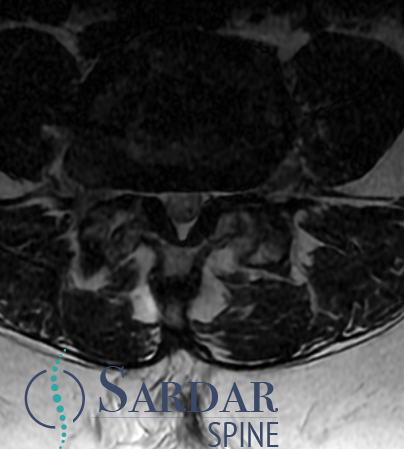

From robotics and AI-driven surgical planning to virtual modeling and custom implants, I’ve embraced a combination of tools that allow me to create tailored surgical plans for my patients—particularly those with scoliosis and spinal deformities.

What sets my approach apart is the seamless integration of these advanced technologies to ensure unparalleled accuracy and better outcomes for each patient.